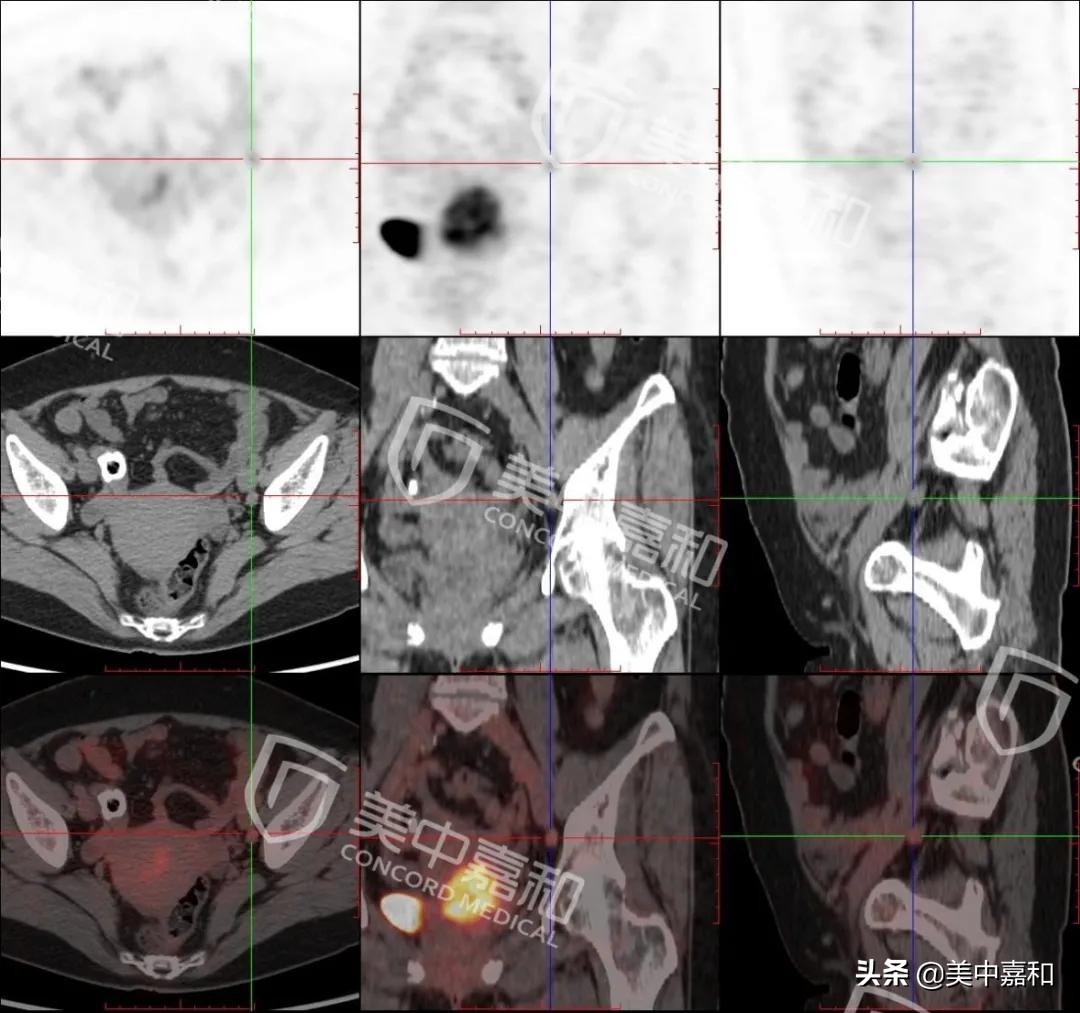

图2:宫颈癌伴左侧髂动脉旁淋巴结转移(T1N1M0)